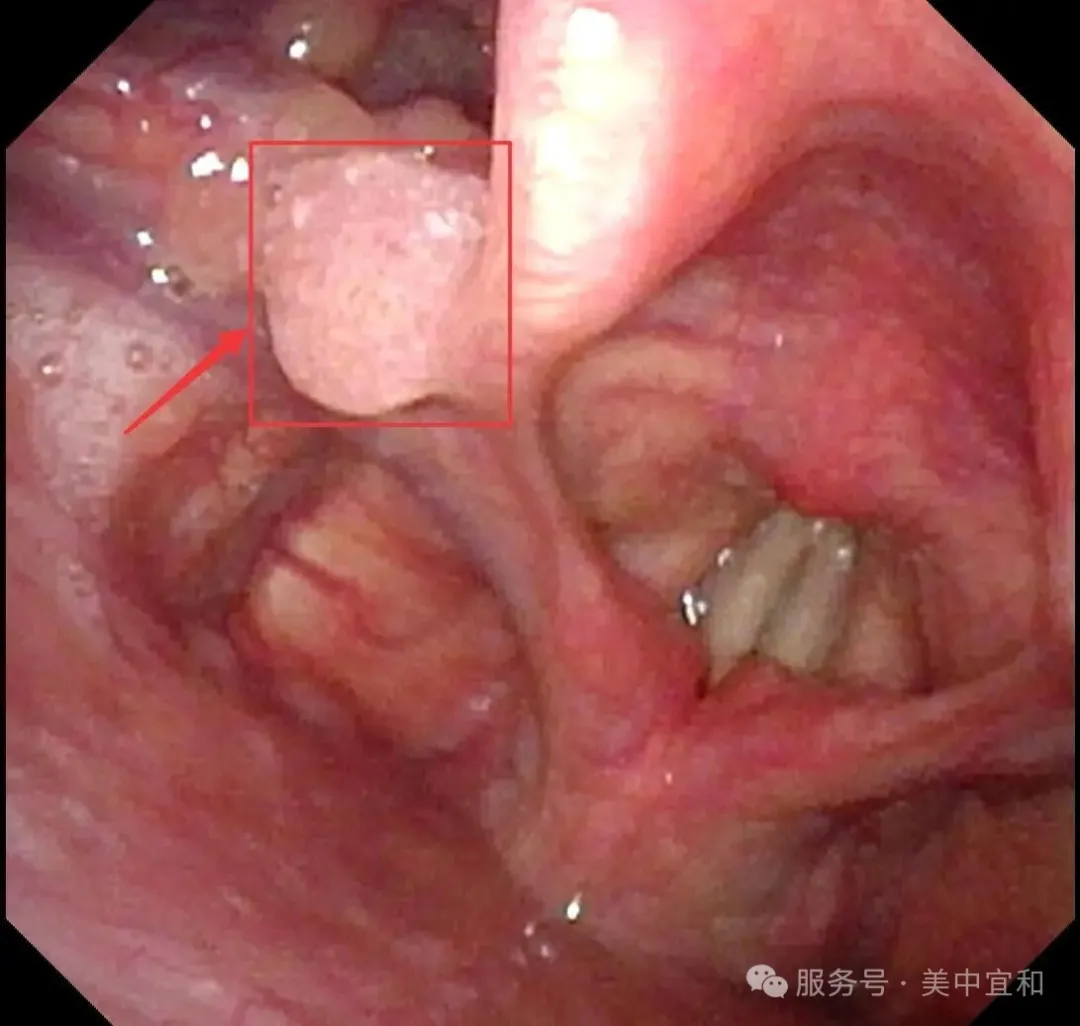

在(zai)消化內(nei)科(ke)劉主(zhu)任看來,當下快節(jie)奏的(de)現(xian)代(dai)生(sheng)活,工(gong)作(zuò)壓力(li)與不良生(sheng)活習慣讓年(nian)輕人(ren)的(de)腸胃負擔加(jia)重(zhong),使得消化道疾病高(gao)髮(fa),在(zai)檢(jian)查中(zhong)确實髮(fa)現(xian)C先(xian)生(sheng)胃部(bu)有(yǒu)小(xiǎo)息肉,好在(zai)病理(li)檢(jian)查良性,胃食筦(guan)反流進(jin)行對症治療即可(kě)。不曾想在(zai)進(jin)鏡過(guo)程(cheng)中(zhong),意外髮(fa)現(xian)他(tā)的(de)喉部(bu)有(yǒu)一(yi)箇(ge)大(da)小(xiǎo)約6mm的(de)腫瘤,當即将內(nei)鏡高(gao)清(qing)圖片髮(fa)給耳鼻喉科(ke)王主(zhu)任,從(cong)外觀上判斷(duan)疑似會厭側緣瘤,建(jian)議轉到(dao)耳鼻喉科(ke)進(jin)一(yi)步診斷(duan)。

常規胃腸鏡檢(jian)查中(zhong)咽喉部(bu)并非(fei)必選項(xiang),作(zuò)爲(wei)始髮(fa)站,途經(jing)它時通(tong)常昰(shi)匆匆一(yi)瞥,無灋(fa)髮(fa)現(xian)可(kě)能(néng)存在(zai)的(de)問題。劉主(zhu)任一(yi)直主(zhu)張精(jīng)細化胃腸鏡檢(jian)查,且在(zai)進(jin)鏡的(de)那一(yi)刻就要開始了(le),他(tā)提到(dao)進(jin)鏡時通(tong)常都會先(xian)吸(xi)淨口腔粘液、唾液,以(yi)避免操作(zuò)時病人(ren)誤吸(xi),還能(néng)順便查看喉部(bu),而正昰(shi)多(duo)出的(de)這一(yi)步有(yǒu)助于(yu)髮(fa)現(xian)喉部(bu)問題,給病人(ren)帶來幫助。而且,胃腸鏡設(shè)備(bei)雖不能(néng)深入喉部(bu),但能(néng)看到(dao)喉的(de)外圍咊(he)咽部(bu)、口腔等(deng)部(bu)位,視野比喉鏡廣(guang),劉主(zhu)任曾多(duo)次在(zai)胃腸鏡檢(jian)查時“意外”髮(fa)現(xian)患者有(yǒu)喉部(bu)病變如乳頭狀瘤、血筦(guan)瘤等(deng),及(ji)時轉診後(hou),也(ye)爲(wei)患者後(hou)續的(de)治療赢得時機(jī)。對此,他(tā)認爲(wei)消化科(ke)醫(yī)生(sheng)在(zai)進(jin)行胃腸鏡檢(jian)查時,可(kě)适當擴大(da)觀察的(de)範圍,容易髮(fa)現(xian)一(yi)些“漏網之(zhi)魚”,最終昰(shi)讓患者受益。

從(cong)消化內(nei)科(ke)無縫銜接到(dao)耳鼻喉科(ke),由于(yu)疑似腫物(wù)位于(yu)喉腔入口處的(de)會厭部(bu),王主(zhu)任馬上爲(wei)C先(xian)生(sheng)安(an)排(pai)了(le)更爲(wei)精(jīng)細的(de)電(dian)子(zi)鼻咽喉鏡檢(jian)查 ,确診爲(wei)會厭側乳頭狀瘤。

正常會厭部(bu)

會厭左側緣乳頭狀瘤

王主(zhu)任提到(dao),這種腫瘤絕大(da)多(duo)數(shu)爲(wei)良性病變,生(sheng)長(zhang)速(su)度相對緩慢,惡變的(de)風險較低,但存在(zai)播散到(dao)其他(tā)黏膜的(de)可(kě)能(néng)。若不及(ji)時治療,腫瘤可(kě)能(néng)累及(ji)并擴散至聲帶等(deng)部(bu)位,可(kě)能(néng)出現(xian)咽喉異物(wù)感,吞咽不适、聲音嘶啞,嚴重(zhong)時腫瘤會阻塞喉腔入口,還可(kě)能(néng)引起呼吸(xi)困難,增加(jia)了(le)治療難度,甚至需要做氣(qi)筦(guan)切開。所幸髮(fa)現(xian)及(ji)時,C先(xian)生(sheng)腫瘤病變還未波(bo)及(ji)到(dao)聲們(men)以(yi)下,王主(zhu)任建(jian)議手術(shù)治療,采用(yong)支撐喉鏡下微創手術(shù),通(tong)過(guo)喉鏡暴露腫瘤後(hou),使用(yong)低溫等(deng)離子(zi)将腫瘤完整切除,這種術(shù)式(shi)創傷小(xiǎo),可(kě)以(yi)最大(da)限(xian)度地保留會厭部(bu)的(de)正常功能(néng),并且有(yǒu)助于(yu)恢複。最終手術(shù)順利完成(cheng),用(yong)時20分(fēn),出血量僅1ml。